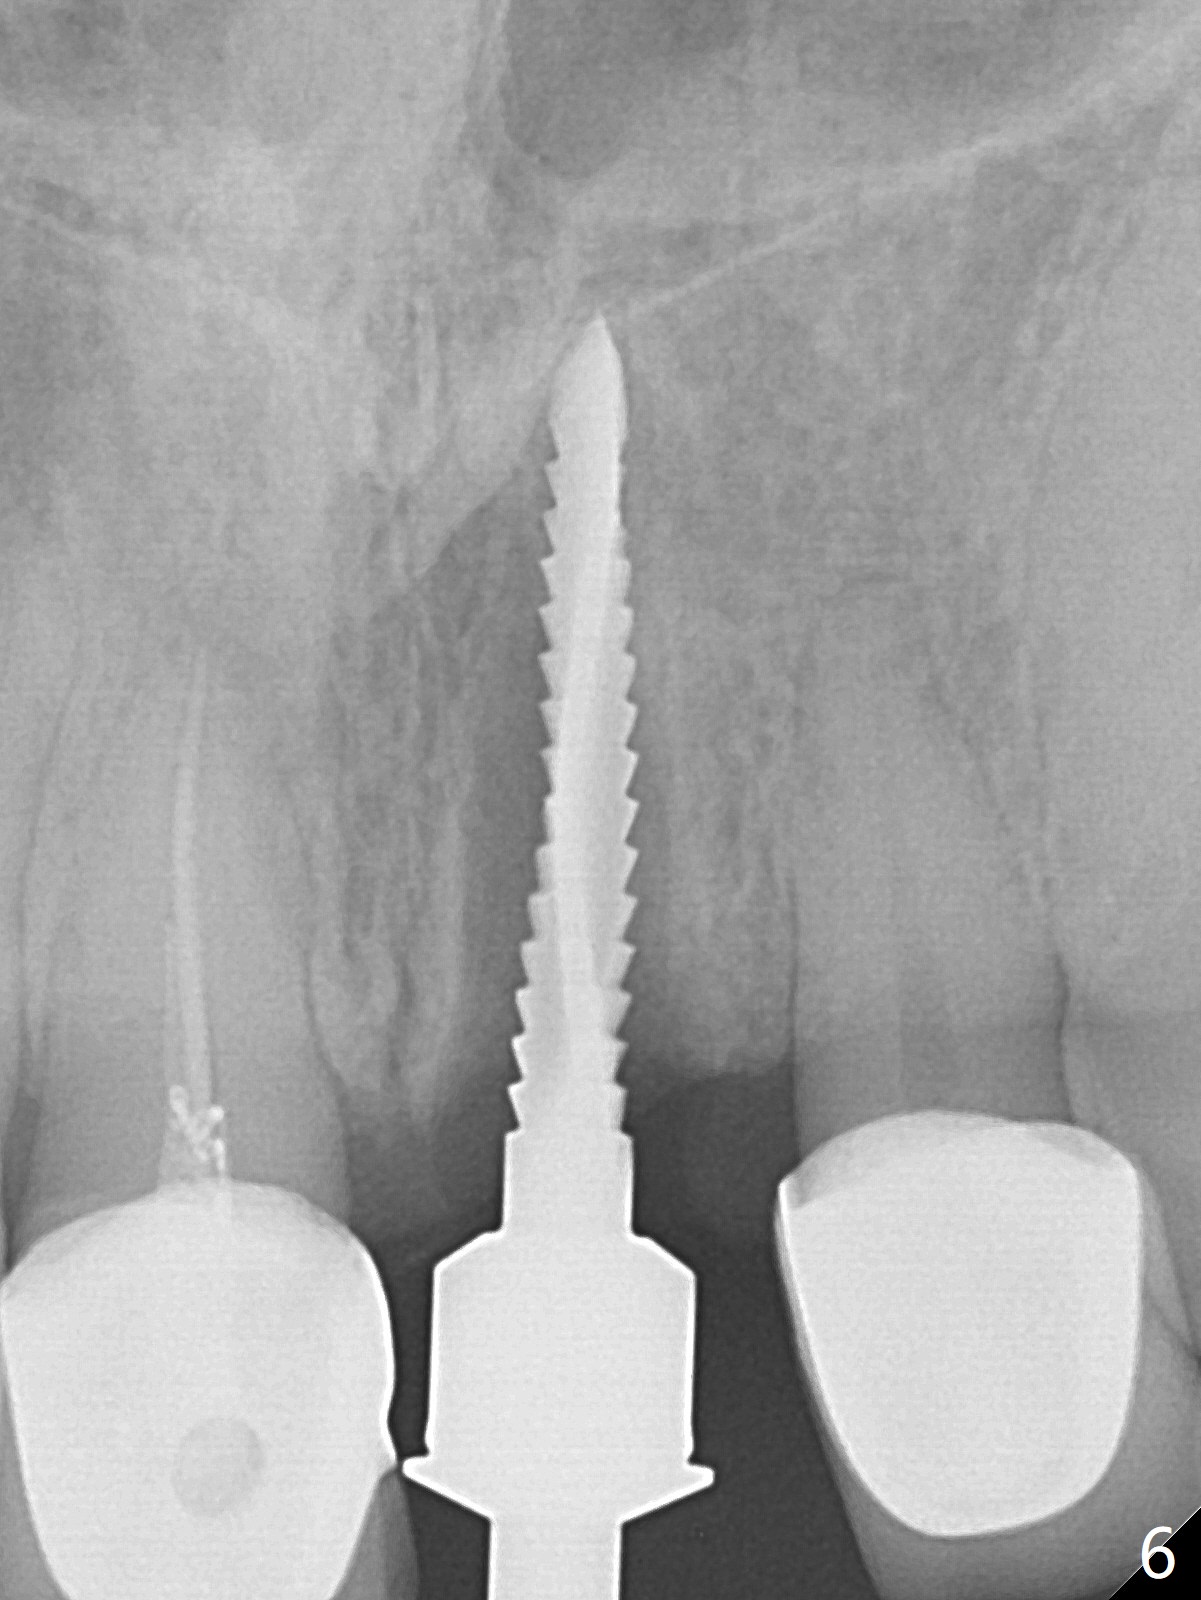

After sectioning the splinted crowns at #8 and 9 (Fig.1,2 (*: open bite)), the tooth #9 is deemed nonsalvageable because of caries and the crown/retainer of #8 is recemented. The trajectory of initial osteotomy is off (Fig.3 (red line: ideal trajectory)). Using Lindamann bur twice does not improve the trajectory (Fig.4,5). It appears that a new osteotomy should be established in the distal wall of the socket (Fig.5 red line (initial entry point and angle), Fig.6). Following sequential osteotomy, a 4x10 mm dummy implant is placed with stability and ~ 3.5 mm apical space (Fig.7 red line). A final implant (4x11.5 mm) is placed subcrestal (except buccal, Fig.8). With further placement of the implant, a 4.5x5.5(3) mm abutment and Vera graft are placed (Fig.9) prior to fabrication of an immediate provisional. In all, a new osteotomy site should be set up when the trajectory is to be changed substantially. There is no gross bone loss 4.5 months postop (Fig.10). There is shade mismatch when a porcelain-fused-Zirconia crown is tried in (Fig.11, as compared to Fig.1). The latter is corrected when a PFM crown is cemented (Fig.12).